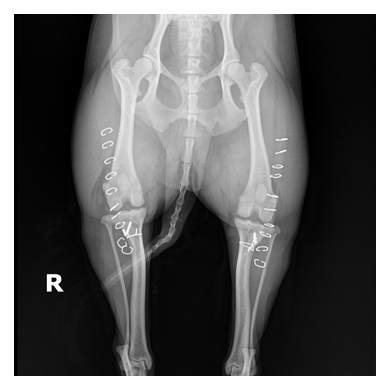

정형외과 케이스

본원은 실력 있는 전문 의료진과 최첨단 시설로 정형외과에서 좋은 예후들을 보여드리고 있습니다. 강아지에게서 쉽게 발생하는 슬개골 탈구, 십자인대 단열 뿐 아니라 다양한 고난도 케이스를 다루고 있으며, 특히 골절 수술은 회복률이 높고 타원 수술 후, 유합부전으로 본원에 내원하여 재수술에 성공한 사례가 많습니다.

대퇴골 복합골절 및 천장골분리골절 전

대퇴골 복합골절 및 천장골분리골절 후

타원 실패 수술 후 2차 수술 전

타원 실패 수술 후 2차 수술 후